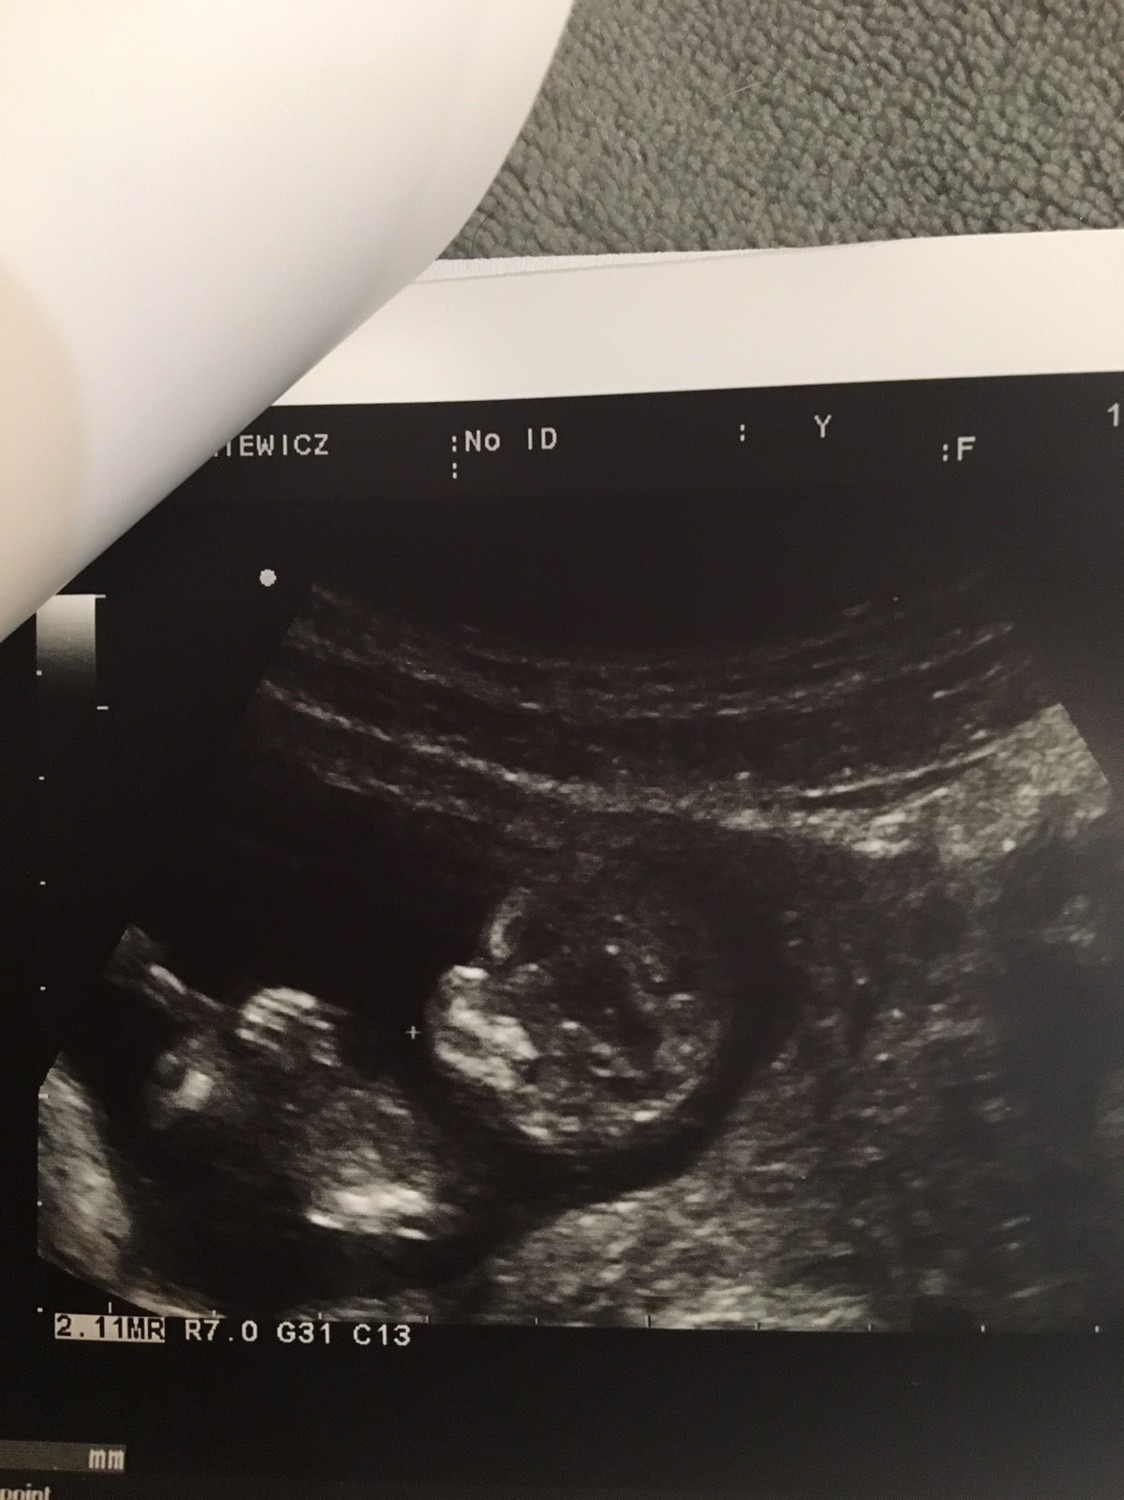

Pierwsze badanie prenatalne to jedyne badanie gdzie uda się zobaczyć a nawet sfotografować całe dzieciątko bo potem będzie już za duże.

Wyglada mniej więcej tak